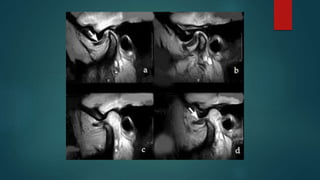

 Estudios de gabinete ( rx, ortopantomografía 2.- Una resonancia

nuclear magnética (RNM) maxilofacial, a nivel de las ATMs)

 La palpación lateral del cóndilo y de los músculos de la

masticación suele ser dolorosa, así como la carga manual aplicada

a la articulación